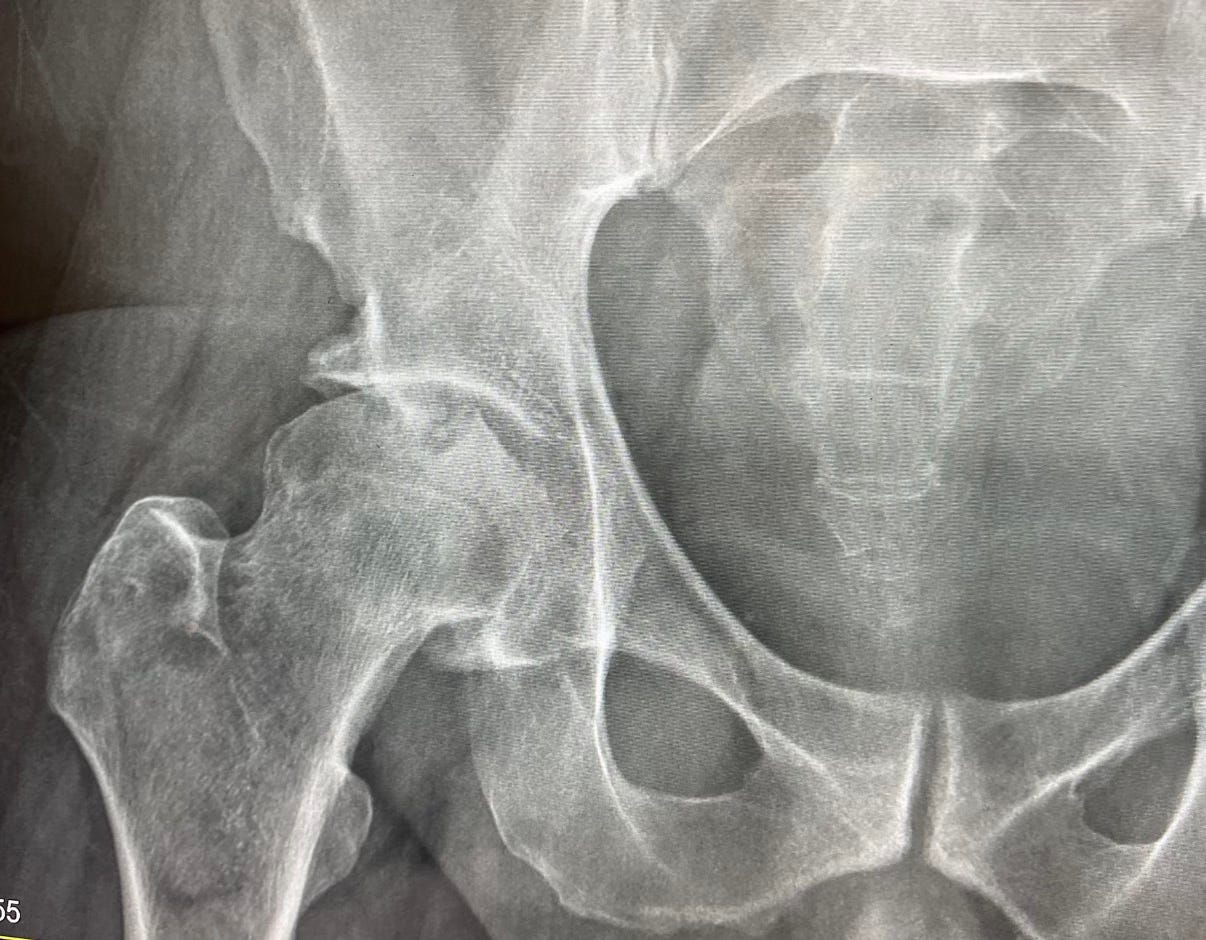

”I had my hip replacement eight weeks ago.”

”You signed off on it and did the pre-op in this office. EKG and all.”

”Not yet, Dr. Burke told me to wait another six weeks. He said three months total so that the hip can bond properly.”

In the past few years, Dr. Amari had assisted in the treatment of my anxiety, weight management, allergies, and hypertension, and ultrasounds were performed on my thyroid and testicles. He also flagged an odd-looking nodule on my left lung via X-ray during my pre-operative screening for my hip replacement and ordered an immediate CT scan be performed.

I made my way to his office, gingerly took the stairs as I let people pass me by. The elevator was non-functional. The incision wound was still fresh, and my hip was swollen up similarly in the shape of a footlong Subway sandwich. My pants didn’t fit right, although I was able to buckle my belt. I had barely showered, and this was the first time I had left the house since my operation. It felt a little too soon to be out. My leg had just been sawn off the week prior.